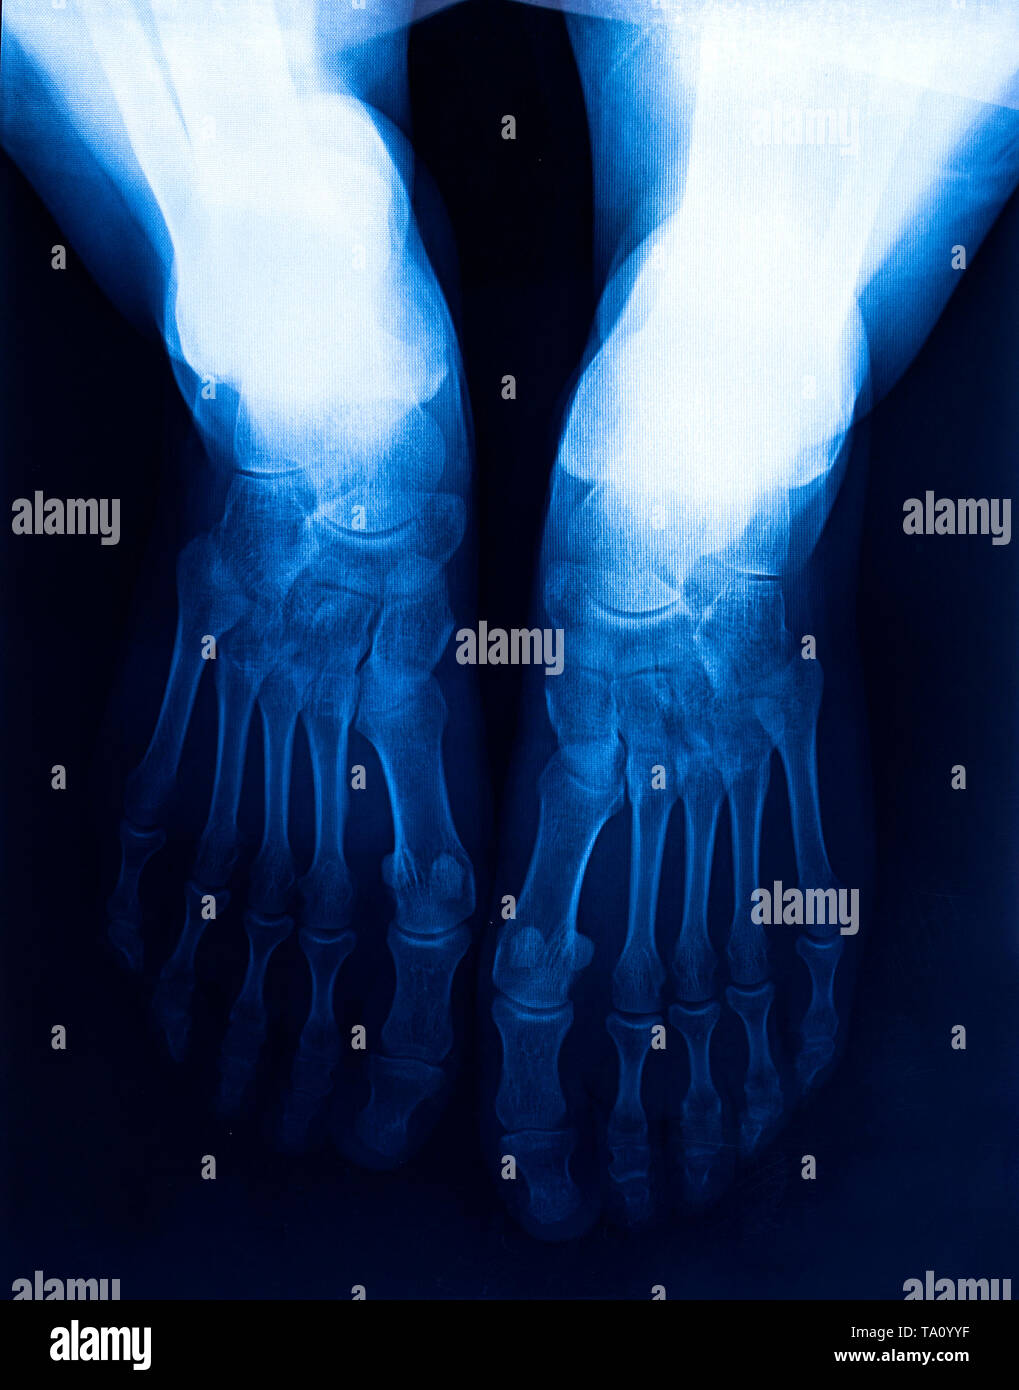

Xray human's ankle with arthritis , top view Stock Photo Alamy Arthritis In Foot X Ray Multiple symmetric joint inflammation in a proximal distribution in the hands or feet without bone proliferation suggests rheumatoid arthritis. Diagnosis is made with plain radiographs of the foot often showing joint space narrowing and dorsal osteophyte formation in the midfoot. Treatment can be nonoperative or operative. When the inflammation is more in a distal. Learn about the causes, symptoms, and. Arthritis In Foot X Ray.

"Rheumatoid arthritis , Gouty arthritis" Xray child's foots and Stock Arthritis In Foot X Ray Learn about the symptoms, causes, and diagnosis of rheumatoid arthritis (ra) of the foot and ankle, a chronic disease that affects multiple joints. This article relates mainly to. Learn about the causes, symptoms, and treatments of arthritis in the foot and ankle, a common condition that affects many joints. When the inflammation is more in a distal. Treatment can be. Arthritis In Foot X Ray.